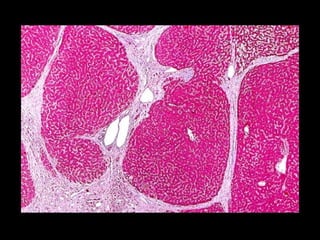

Alterações Circulatórias do Fígado  Congestão Hepática Passiva Crônica    I.C.C. Direita    Fígado em Noz-Moscada

Alterações Circulatórias doFígado  Congestão Hepática Passiva Crônica  I.C.C. Direita  Fígado em Noz-Moscada